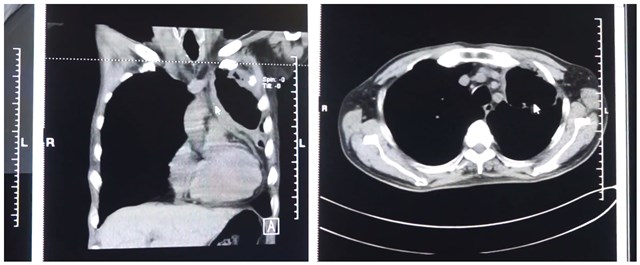

手术前CT

2020年3月11日,龚叔来到广州复大肿瘤医院就诊,检查发现其肿瘤较前进展,因服药期间有间断咳血,医生建议后续停止口服安罗替尼。针对龚叔的病情,我院介入科周强副主任医师、杨清峰和钟小军主治医师等人立马组织会诊,给予龚叔平喘、止咳、化痰、雾化、减低心律等对症治疗,随后在局麻下进行介入化疗及介入栓塞术,治疗过程顺利。